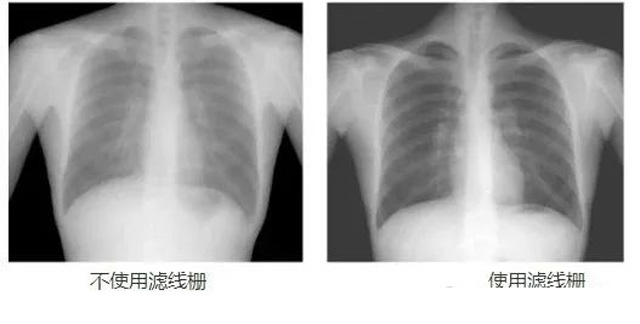

DR影像X射線在醫學檢查成像有著廣泛的使用。但是它的散射線影響成像質量問題。濾線柵的發明使用很好的解決了這個問題,構造簡單鉛條粗,密度和柵比規格單一,能減散射線但吸收較多原發射線。伴隨這醫療影像設備技術的發展,這個濾線柵的工藝制造技術有改進,鉛條變薄,柵密度和柵比有更多的選擇。特別是材料方面有新組合,填充物也依不同成像要求優化。特別是移動DR這類型的DR設備的出現,濾線柵也設計成立方便拆卸形的,方便使用。被照體情況決定是否使用,更好平衡成像質量與射線劑量。

焦距(f):斷面看鉛條延長線會聚點到柵板垂直距離,即柵板焦距(半徑)。柵密度(N):每厘米范圍內含有的鉛條數,一般40~65線/cm。柵比(R):鉛條高度與柵條間隙之比,比值越高濾除散射線能力越強,一般8:1~14:1之間。結構組成:3~5mm薄板,用0.05~0.1mm鉛條,夾持在鋁或紙之間平行或按斜率排列,相鄰鉛條間用易透X線物質填充定位、黏合,如木、紙、鋁片等。

放置方面:置于人體與片盒間,聚焦面朝向X線入射方向,X線焦點放鉛條會聚線上,不能反置,X線中心對準濾線柵中心,左右偏移不超3cm,傾斜X線管要與鉛條排列方向平行。攝影時焦距改變不超焦距的25%;活動式濾線器運動時間至少長于曝光時間的1/5;因吸收原發射線要適當增加曝光條件;四肢薄位置一般不用濾線柵;不同千伏對應不同柵比;立位胸片架、乳腺DR攝影等有各自特定濾線柵要求。